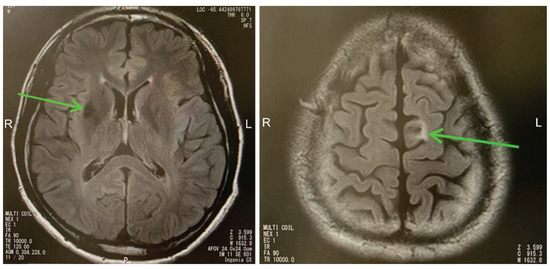

2.1. Case 1